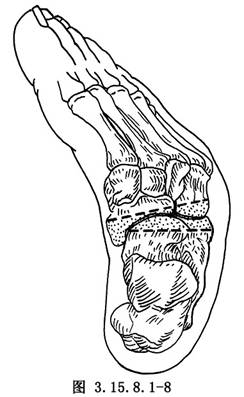

6.5.3 3.截骨矫形

先用骨刀截除跟骰关节和距舟关节,楔形截骨基底在背外侧纠正内翻畸形(图3.15.8.1-8),切除角度等于X线片第2趾和足中线形成的角度(图3.15.8.1-9)。若纠正足外翻畸形,楔形截骨基底可设计在内侧(图3.15.8.1-10),由于距舟关节和跟骰关节在一个平面上,切除角度是一致的(图3.15.8.1-11)。最后切除距下关节,纠正跟骨内收(图3.15.8.1-12),根据X线片胫骨中线和跟骨中线形成的角度,做外侧楔形切除(图3.15.8.1-13)。当骨刀切到对侧时,注意轻缓,尤其纠正外翻时,更要注意防止误伤胫后的血管及神经(图3.15.8.1-14)。将已切除的骨面合拢,如畸形纠正,骨面能紧密对合(图3.15.8.1-15),周围空隙植入切除多余的松质骨。